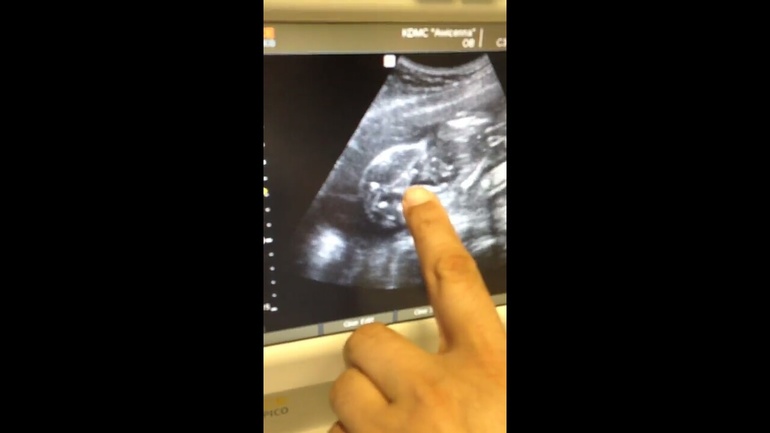

Да, мальчик как есть. Хорошенький причиндал 😊

Ну точно не пуповина) Девочку хотели?

да сначала как то да, думали о девочке, потом сказали мальчик, и как то так обрадовались, и к мысли привыкли что мальчик) не хочется сюрпризов 😁

Ой, а я наоборот, вроде и рада второй дочке, но где то там в глубине души очень надеюсь на ошибку узи) Но у меня тоже явно прям пирожок показали. Не перепутаешь. Такого как у вас нету точно) Но все же...🙏🏻

Это 100% мальчик. У меня их двое. Сейчас в третье Б впервые увидела пирожок... он очень отличается от вашей сардельки..😉